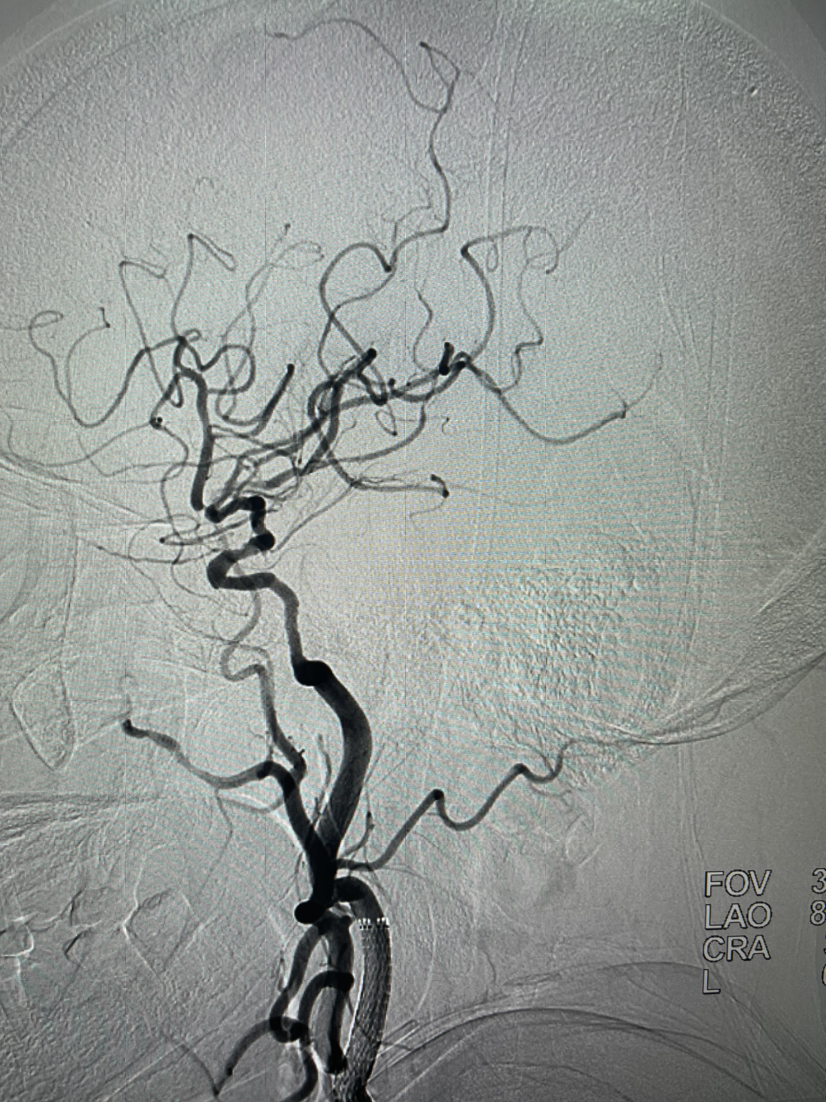

颈内动脉正位造影左侧大脑前动脉缺如

颈内动脉侧位起始部重度狭窄,大脑中M2重度狭窄